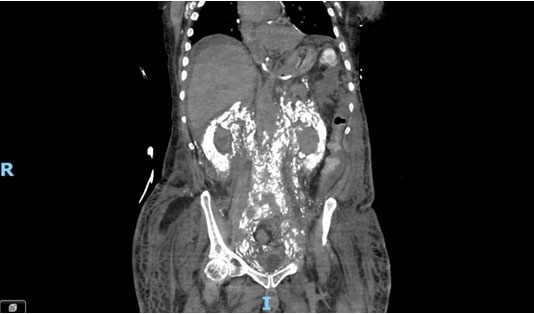

Computed tomography imaging (Figure 1 and Figure 2) revealed extensive systemic amyloidosis, progressing from previous scans with notable deposition surrounding the renal parenchyma and throughout the retroperitoneum. There were also prominent amyloid deposits along the path of the ureters, infiltrating the ureteral tissue itself, as well as periureteral tissue, and nearby lymphatics. This deposition of amyloid contributed to the patients AKI through chronic hydronephrosis and likely caused intrinsic kidney injury through amyloid deposition in the renal parenchyma, which may have been compounded by some element of obstruction from diffuse retroperitoneal amyloid deposition. The patient was managed with continuous renal replacement therapy, but ultimately elected for hospice care and passed due to renal failure.

Figure 2: Coronal CT demonstrating diffuse retroperitoneal calcified amyloid deposition.